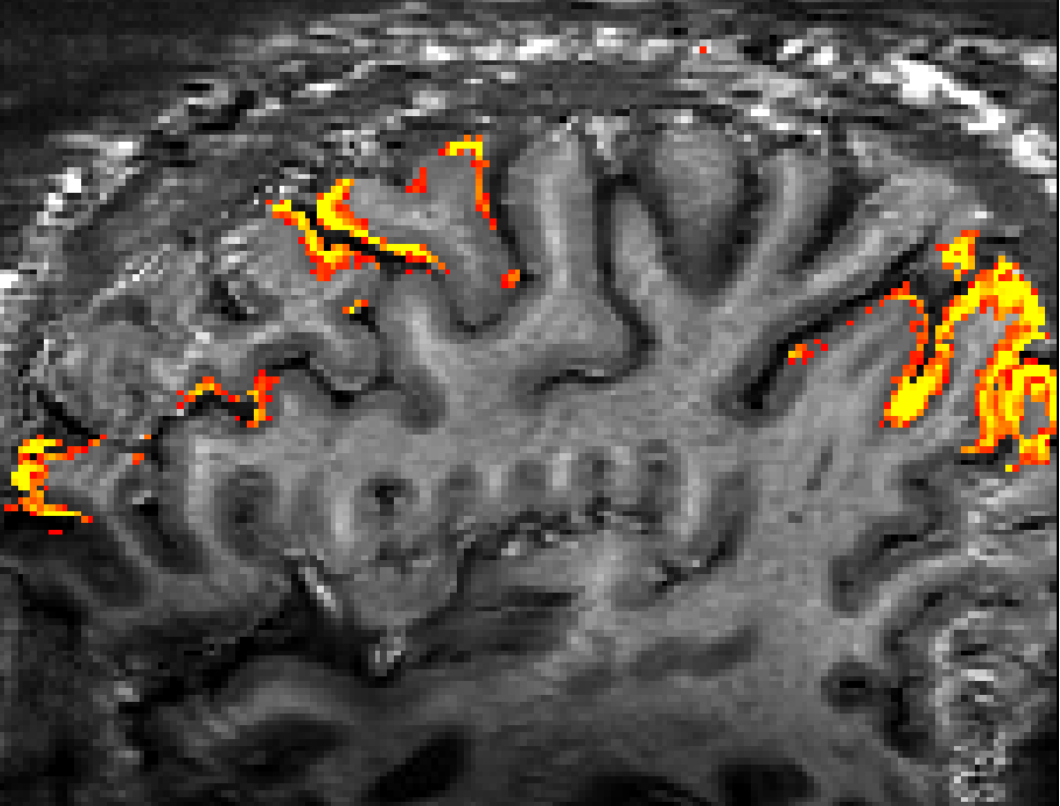

- Ruediger Strinberg and Tony Stoecker implemented a VASO sequence with segmented 3D-EPI readout for SIEMENS VE systems.

Data of this figure were acquired with Stirnberg’s sequence at the 7T Terra at NIH.